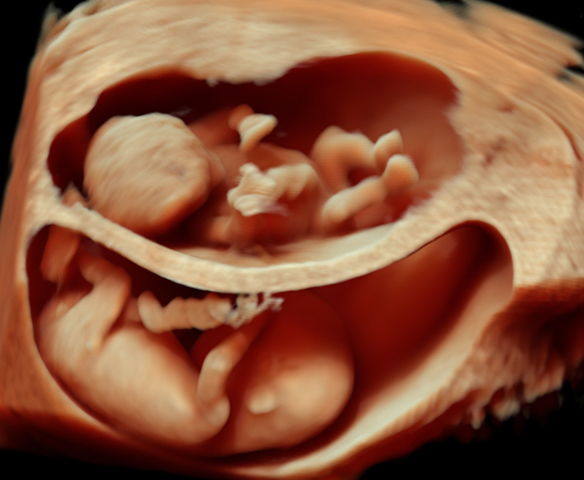

产科_胎儿_早孕单胎三维成像

产科_胎儿_早孕双胎三维成像